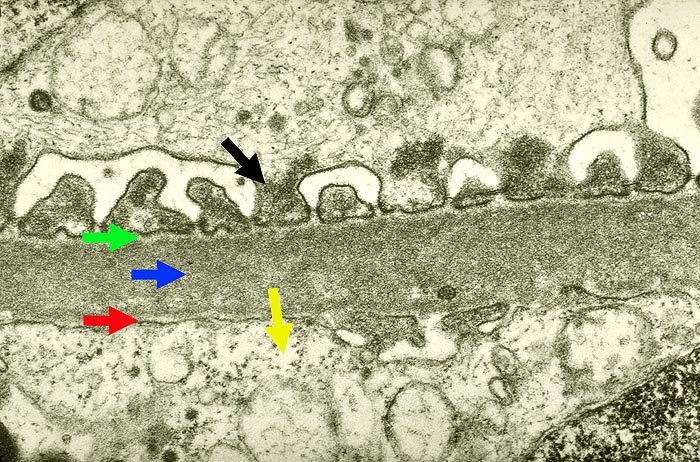

Morphologisch handelt es sich bei der membrano-proliferativen Glomerulonephritis um eine durch Mesangium- und Kapillarwandschädigungen charakterisierte Immunkomplexglomerulonephritis (Synonym: mesangiokapilläre Glomerulonephritis). Man unterscheidet einen Typ I mit subendothelialen Depots (> 2696) von einem Typ II mit dichten intramembranösen Ablagerungen (besser als intramembranöse Glomerulonephritis oder dense deposit disease bezeichnet) (> 2264).

Die Erkrankung läuft phasenhaft ab (> 2630): initial subendotheliale Depots begleitet von neutrophilen Granulozyten und Monozyten in den Schlingenlumina (> 2636), später mesangiale Zellvermehrung, Auswandern in die Schlingenperipherie (mesangiale Interposition) und subendotheliale Basalmembranneubildung (Tramgleisbild aufgrund einer Basalmembranverdopplung). Schliesslich Abnahme der subendothelialen Depots und zunehmende mesangiale Matrixvermehrung zum Teil mit knotiger Umwandlung der Mesangiumfelder.

Elektronenmikroskopisch hauptsächlich subendotheliale, später auch mesangiale (> 2690) und gelegentlich einzelne subepitheliale Depots.

Die präzise Diagnosestellung glomerulärer Erkrankungen erfordert neben der Berücksichtigung klinischer Angaben den kombinierten Einsatz von Lichtmikroskopie, Elektronenmikroskopie und Immunhistochemie.